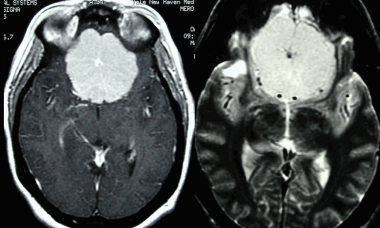

Метастазы головного мозга на МРТ. Фото. Определяются множественные метастазы в мозг при раке легкого: слева в режиме Т1-ВИ в виде гипоинтенсивных образований, справа — в режиме Т2-ВИ виде множественных участков повышенного сигнала, окруженных зоной перифокального отека. У пациента подтверждена первичная опухоль легкого.